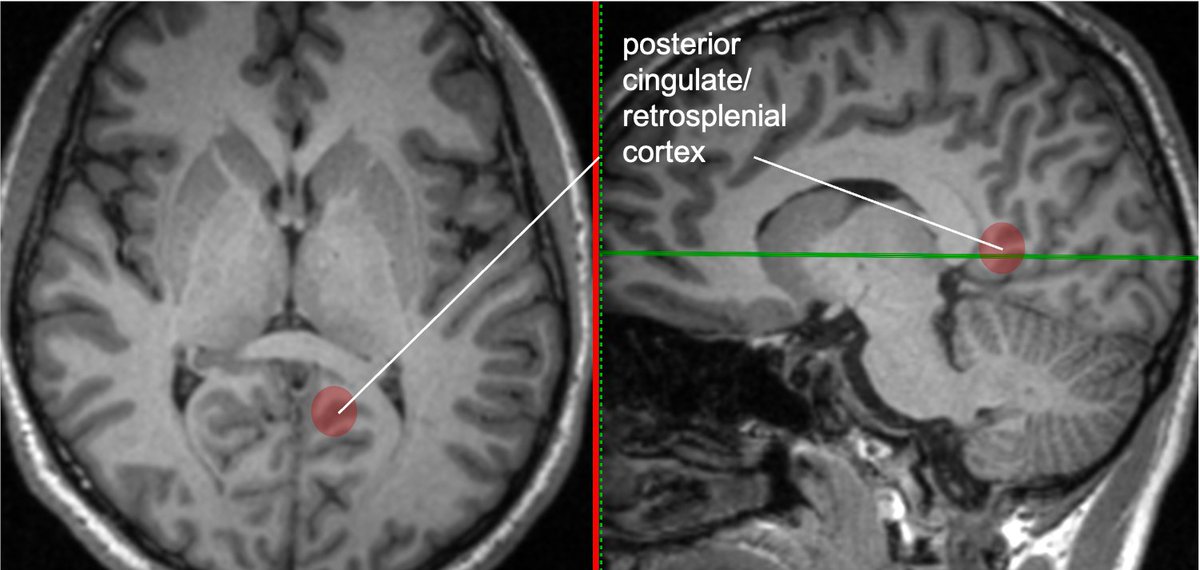

The lingual gyrus is involved in holistic visual and word processing, encoding visual memories, imagery, and dreaming. The ganglioglioma in the shown case is centered in the lingual gyrus.

Cingulate g. is part of the limbic circuit; the post cingulate cortex (PCC) is important in default mode network, awareness, pain, and episodic memory retrieval. PCC including the retrosplenial cortex (which together some call restrosplenial gyrus) is involved by the tumor. 11/13